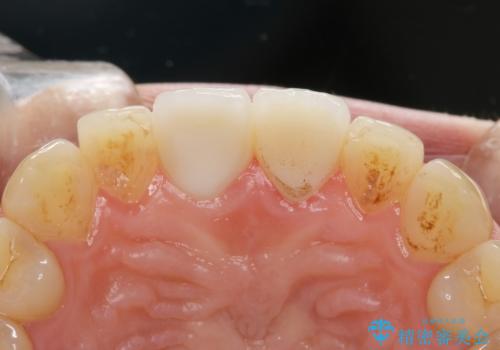

- 右上の前歯が折れたことを主訴に来院された患者様です。

歯が折れた部分は他院により応急処置で仮止めされていました。

欠けた範囲が大きかったため、セラミッククラウンによる補綴治療を行いました。